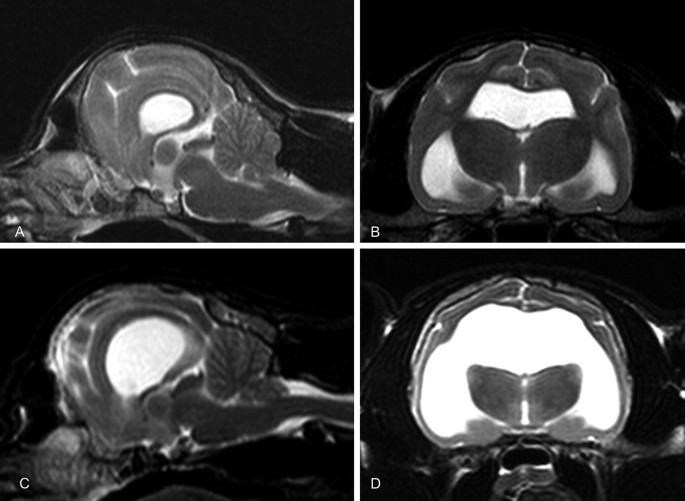

Hydrocephalus In Animals Springerlink